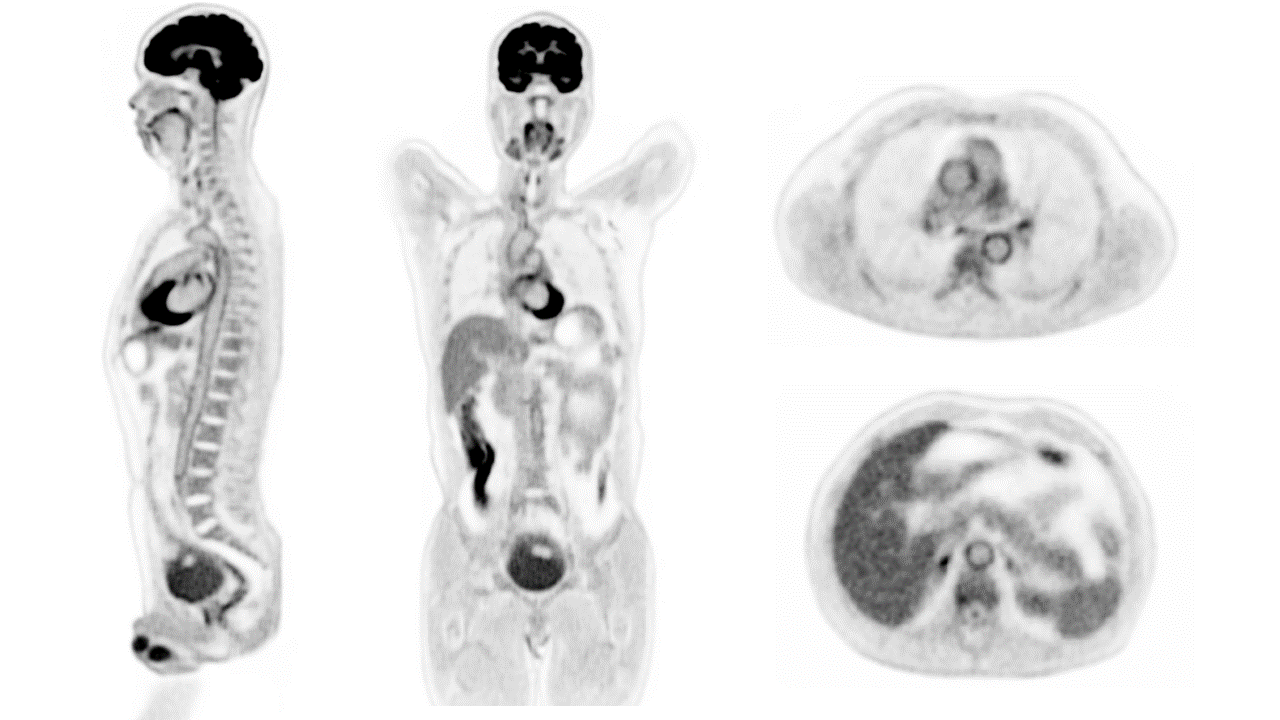

Le scanner Explorer a enfin réalisé sa première image en 3 dimensions d’un corps humain entier. Le 19 novembre, cet appareil de radiologie installé à l’UC Davis Health (Californie) a pour la première fois permis de voir les os et organes d’une personne au cours d’une même radio.

La prise de vue a été publiée sur YouTube par Simon Cherry, un ingénieur biomédical qui travaille sur Explorer. Sa vidéo permet d’admirer la photographie en 3 dimensions d’un corps scanné qui pivote sur lui même, faisant apparaître son ossature et ses organes.

Ces 2 techniques permettent à Explorer d’obtenir une image efficace en une seconde. « Le niveau de détail était incroyable […]. Il n’existe aucun autre appareil capable d’obtenir de telles données chez l’homme, c’est vraiment nouveau », assure Ramsey Badawi, l’autre ingénieur biomédical en charge d’Explorer à l’UC Davis Health.